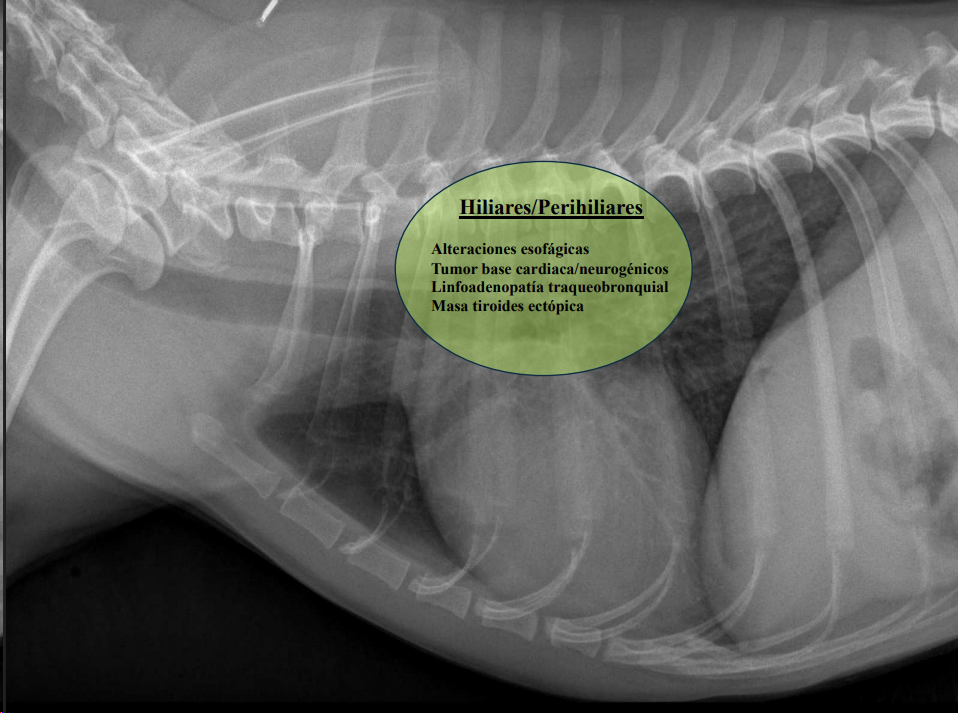

- Masas mediastínicas (craneodorsales, hilares, caudodorsales, caudoventrales, craneoventrales).

Hiliares/Perihiliares: alteraciones esofágicas, tumor base cardiaca, linfoadenopatía traqueobronquial, masa tiroidea ectópica.

-

Masa de opacidad tejido blando que desplaza la traquea y la bifurcación bronquial.

Puede ser por los nodulos parabronquiales, esofagico o por masa en el pulmón